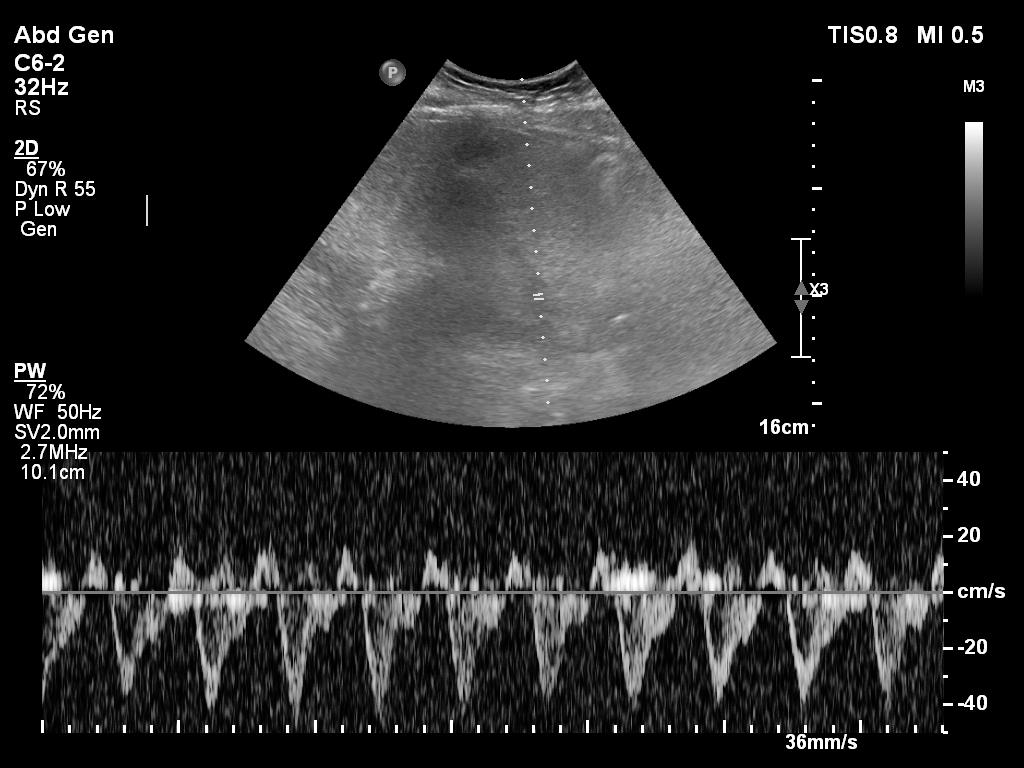

8/ and VEXUS...although not easy and quality not ideal

hepatic vein

9/ portal vein

10/ renal vein (or not :)